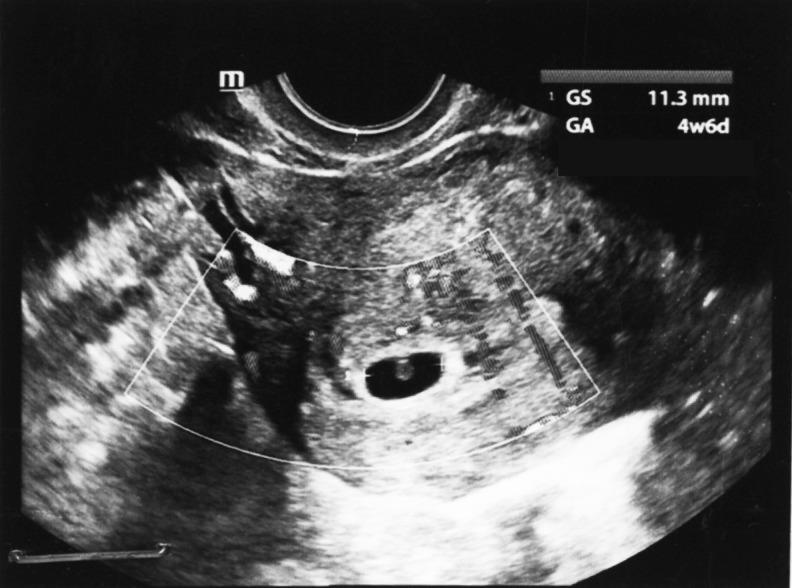

Infertility is a medical and psychosocial problem with a high prevalence. There are different treatments for this problem in Iranian traditional medicine. A 28-year-old woman presented with the complaints of 4 emergency operations of the left ovarian cyst during 4 years and infertility. Diagnostic laparoscopy showed an ovarian cyst, adhesion, and endometriosis. Hysteroscopy was unremarkable. After 2 months of letrozole administration, the ovarian cyst ruptured again. Considering the failure of conventional treatments, Iranian traditional medicine products were administered to the patient. After 3 months, the patient conceived and delivered a healthy boy through normal vaginal delivery. These compounds may help with pregnancy as a uterine tonic, vitalizer, and aphrodisiac with brain and cardiac tonic properties.

不孕症是一个患病率很高的医学和社会心理问题。伊朗传统医学对这一问题有不同的治疗方法。一名28岁女性因4年内左侧卵巢囊肿进行了4次急诊手术及不孕症前来就诊。诊断性腹腔镜检查显示有卵巢囊肿、粘连和子宫内膜异位症。宫腔镜检查未见异常。服用来曲唑2个月后,卵巢囊肿再次破裂。考虑到传统治疗方法失败,给该患者使用了伊朗传统医药产品。3个月后,患者怀孕并通过正常阴道分娩产下一名健康男婴。这些化合物作为子宫滋补剂、活力剂和具有脑和心脏滋补特性的壮阳剂可能有助于受孕。